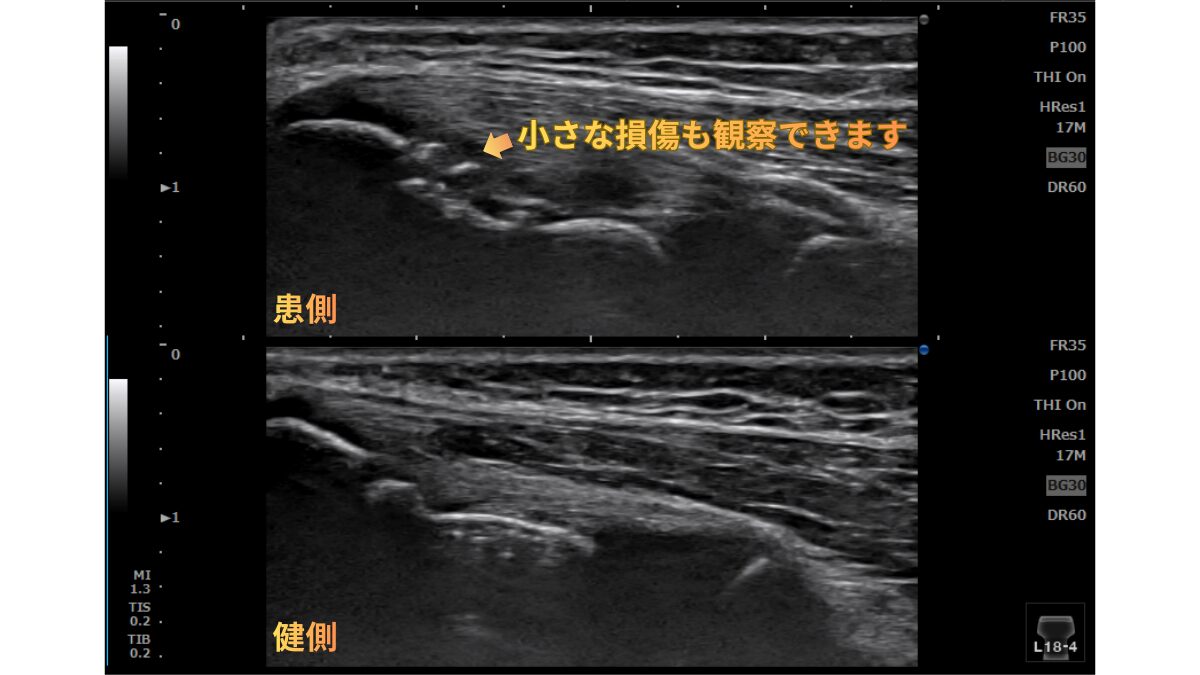

当院のこだわり:極めて鮮明な解像度

当院が採用しているプローブは、怪我の多い「表層3〜4cm」の状態を驚くほど鮮明に映し出す特殊仕様(コニカミノルタ L18-4)です。微細な肉離れや、レントゲンでは見逃されがちな軟骨の損傷も正確に捉えます。

野球肘・内側上顆骨折のエコー画像

▲ エコーで捉えた内側上顆(骨端核)の損傷。微細な骨の連続性の不全を可視化しています。

中学生の野球選手。投球中にはっきりと「痛めた瞬間」を覚えているケースでした。この記憶がある場合は急性外傷の可能性が高いため、即座に精密検査が必要です。

【エコー所見】

内側上顆(成長期特有の骨端核部分)の損傷を可視化。骨の不整や、周囲の炎症反応を客観的に評価しました。